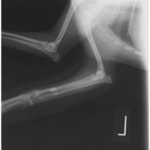

ペルシャ猫 11ヶ月齢 雄

他院にて左大腿骨遠位の成長板骨折(salter-harrisⅠ型)が認められており、治療相談を目的として来院。当院にて、キルシュナーワイヤーを用いたピンニングにより骨折部位の整復を行いました。術後の経過は良好で、現在も経過観察中です。

術前レントゲン